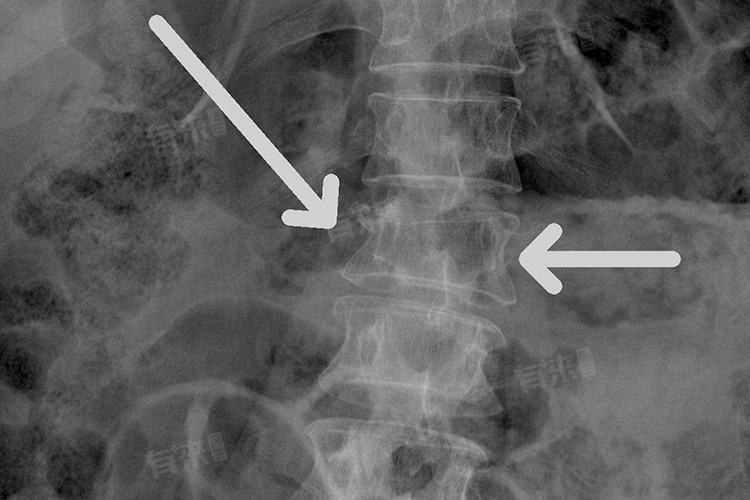

- X线检查是初步诊断的首选方法,可清晰显示腰椎的整体形态、骨折部位、压缩程度及骨折类型,判断椎体高度丢失情况和有无脱位。但X线对骨折细节及椎管内情况显示不佳,需结合其他检查进一步评估。